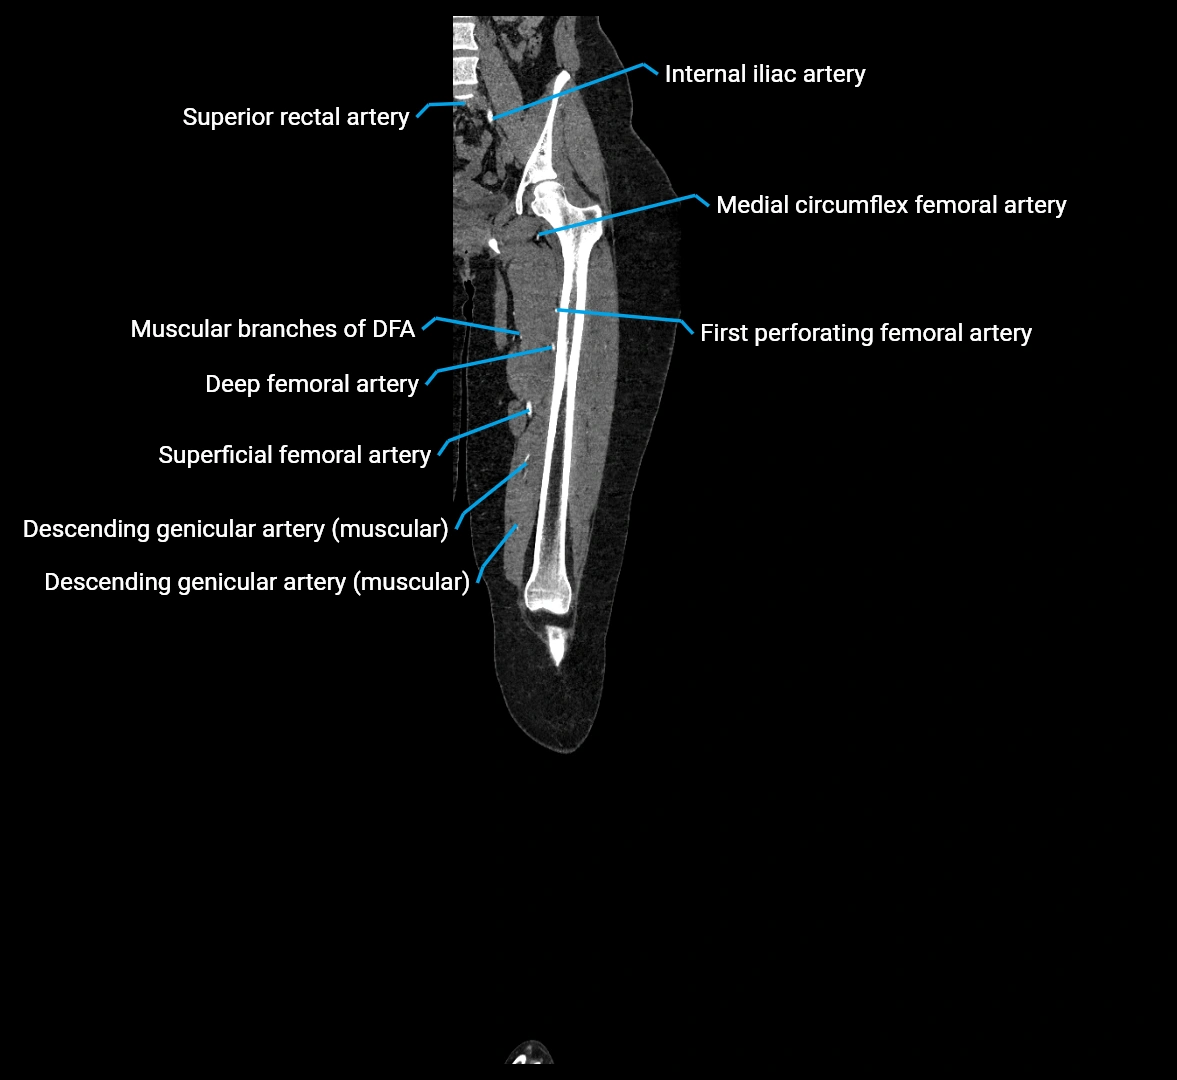

Contrast-enhanced CT (CTA):

• Gold standard for abdominal aortic imaging

• Provides excellent detail of lumen, wall, aneurysm, thrombus, and branch vessels

• Multiplanar and 3D reconstructions help in aneurysm measurement, stent graft planning, and dissection evaluation

• Detects acute rupture, traumatic injury, or occlusion with high sensitivity